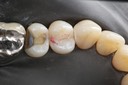

Gary Umeda #3,4,5 pre-op

Gary Umeda #3-4 pre-op